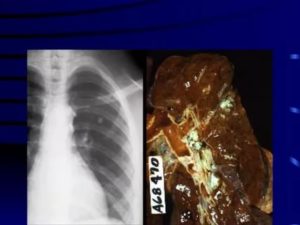

Очаг Гона в легких является результатом первичного инфицирования человека микобактерией туберкулеза. Длительность его формирования в среднем составляет до 3 лет. Очаг Гона представляет собой овальное образование, иногда с неровными лучистыми контурами. Структура его представлена соединительной тканью, коллагеновыми волокнами, отложениями кальция. Размеры могут достигать 2 см.

Наиболее частый путь формирования очага Гона в легком – фиброзная трансформация. Сущность этого механизма заключается в прорастании гранулемы соединительной тканью и последующее образование рубца. Перифокальное воспаление постепенно проходит.

Трансформация идет от краев капсулы к центру, фрагментируя туберкулезные бугорки. В таких случаях обнаруживаются промежуточные формы МБТ, что играет важную роль при рецидивировании инфекции. После полной кальцинации очагов возбудитель не выделяется.

При рентгенологических исследованиях очаг Гона представляет собой затемнение овальной (реже округлой) формы с резкими очертаниями, размерами до 5 мм. Образования могут быть единичными и множественными. Излюбленная их локализация – нижние и средние отделы легких. Иногда контуры очага могут быть неровные. Легочный рисунок неизменен, корень не расширен.

На разных этапах петрификации (обызвествления) очага Гона изменяется, структура его может быть:

- гомогенной (однородной),

- негомогенной: имеет зернистое или дольчатое строение, неровные границы.